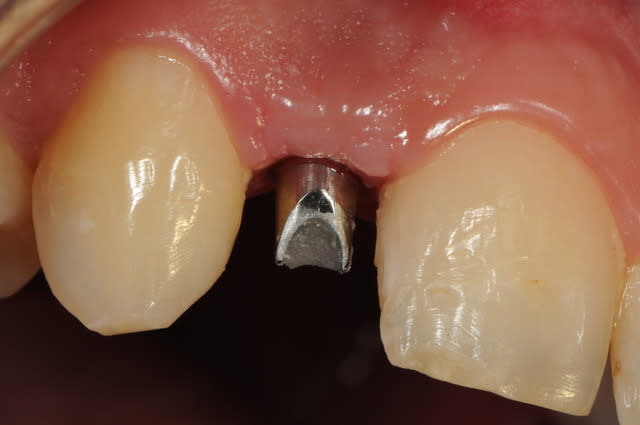

01/09/2010 à 16h54

-1 ou 2 mois plus tard ( je sais plus)

- empreinte avec transfert pop in

- pilier zircone esthétique Axiom

- prothèse et pilier

- pilier zircone en place

- couronne en place (petite compression gingivale)

fin du traitement